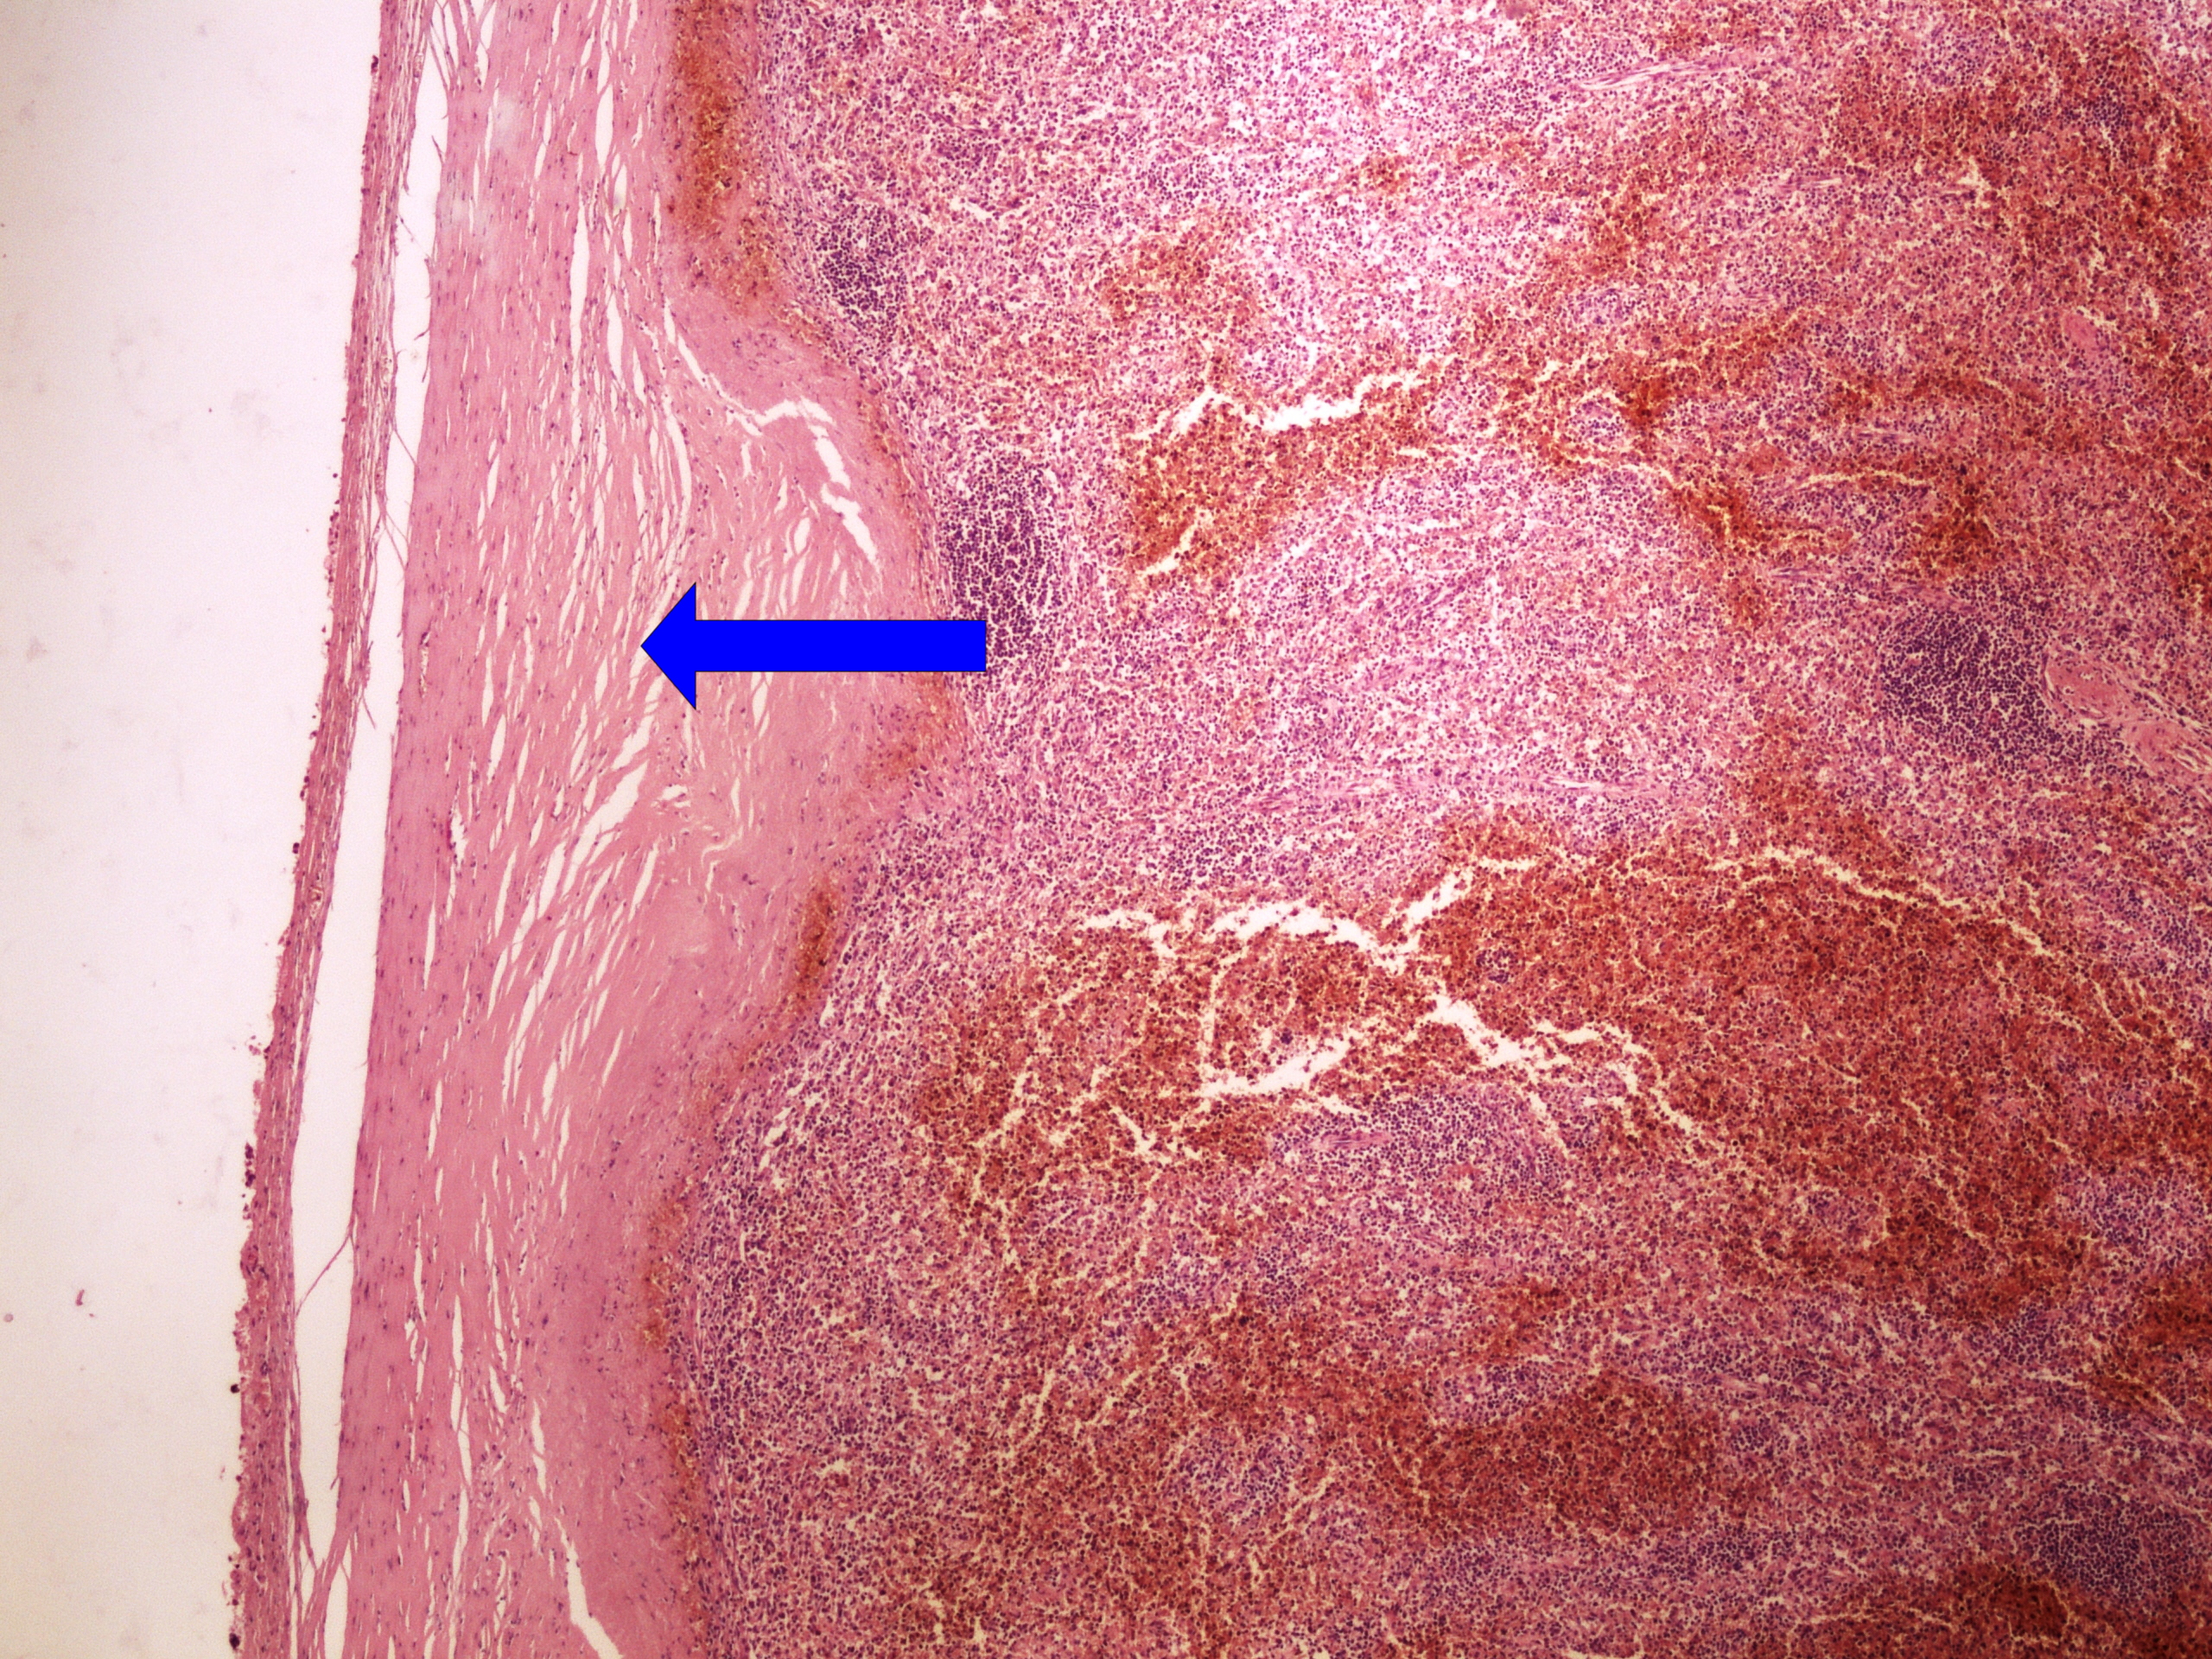

Preparát č.17 a č.18 - perisplenitis cartilaginea

Struktury

- ložiska vaziva